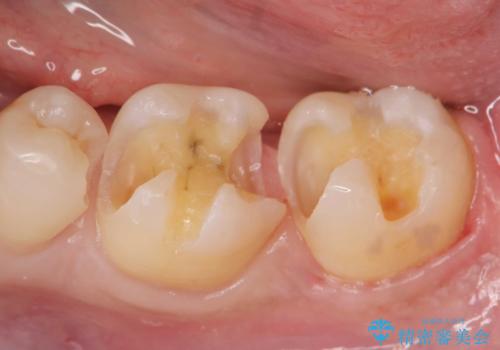

- 12万円 ゴールドインレー×2費用は治療当時の料金となります

ゴールドインレーについて

ゴールドは見た目に難がありますが、歯を削る量がセラミックに比べて少ない・複雑な形にも追従しやすい・壊れにくいなどの利点があります。